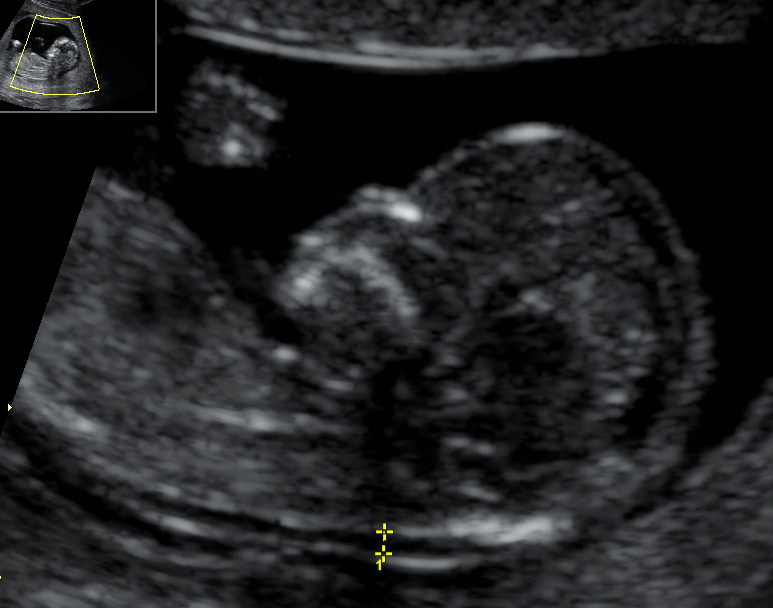

エコー ダウン症 むくみ. ダウン症 nt エコー , ダウン症の特徴的な所見が エコーでも見られることがあります。 その特徴的な所見は後頚部の腫れです。 nuchal translucencyを略して 「nt」と呼ばれることもあります。 ntはリンパ液が溜まった状態です。 妊娠11. 妊娠初期のエコー検査で調べた ntの数値と妊婦の年齢、 妊婦の血液検査など 具体的には、エコー写真で胎児を正面から撮影して横から見た画像では、ダウン症の場合は後頭部から首にかけてむくみが厚いことが多いです。. ダウン症はエコー中に舌を出すのか? ダウン症がエコーでわかる確率は何%!? ダウン症の子をエコーで見た動き方は!? ダウン症はエコーでみたら足の特徴でわかるのか!? ダウン症はエコーでいつから判明するのか? ダウン症はエコーで11週目から.

ダウン症のエコー写真の特徴:手 ダウン症を見分けよう!エコー写真の特徴 コメントを残す 返信をキャンセルする。 名前 サブコンテンツ サイドバー 目次 サイト内検索 ダウン症の予防には葉酸が大事 子育てママ応援本 新着記事. ダウン症の胎児については様々な情報が出ています。 エコー写真に写っている姿から判断するものも多くあるのですが、 その代表的なものがntと呼ばれる頸部の浮腫です。 首にできてしまった浮腫が大きい場合、 ダウン症であることを疑われるのですが、 浮腫が.